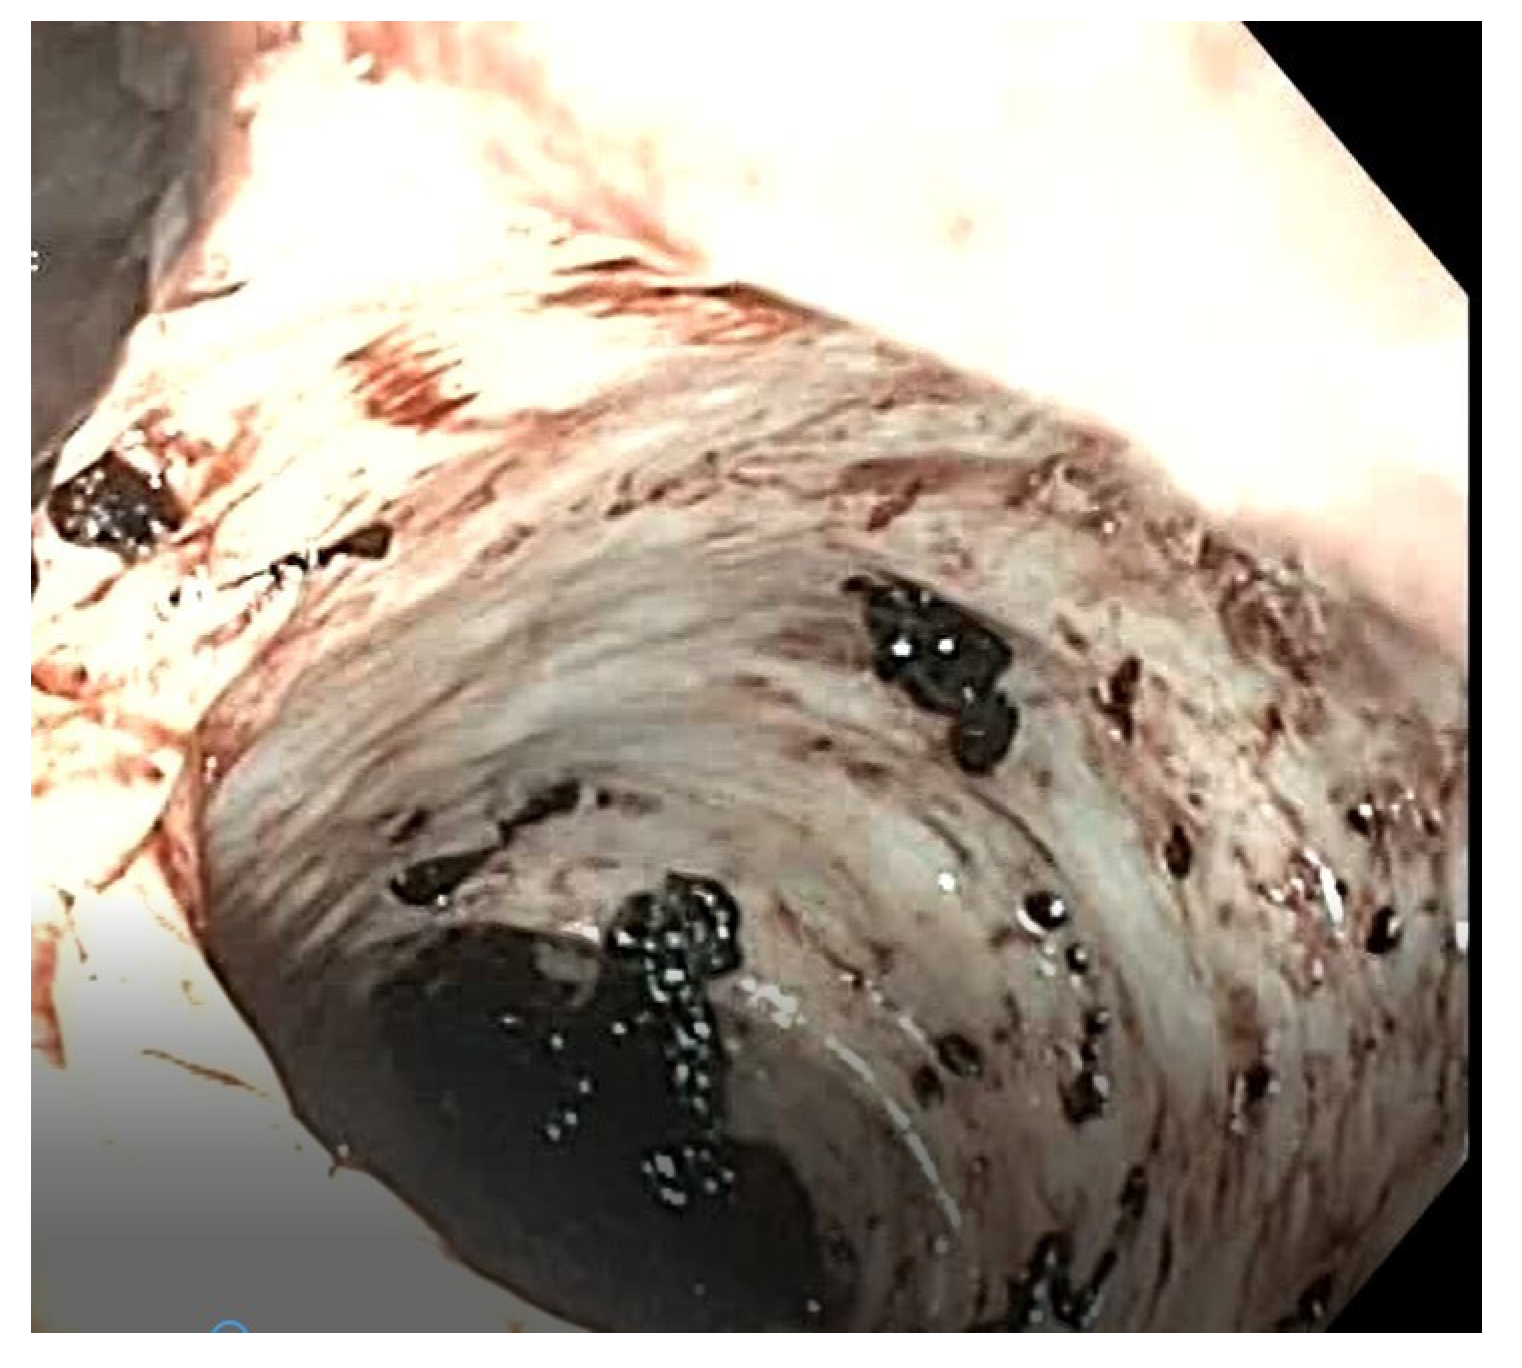

Figure 1.

Case 1—US showing the thickened wall of the suspected Meckel’s diverticulum.